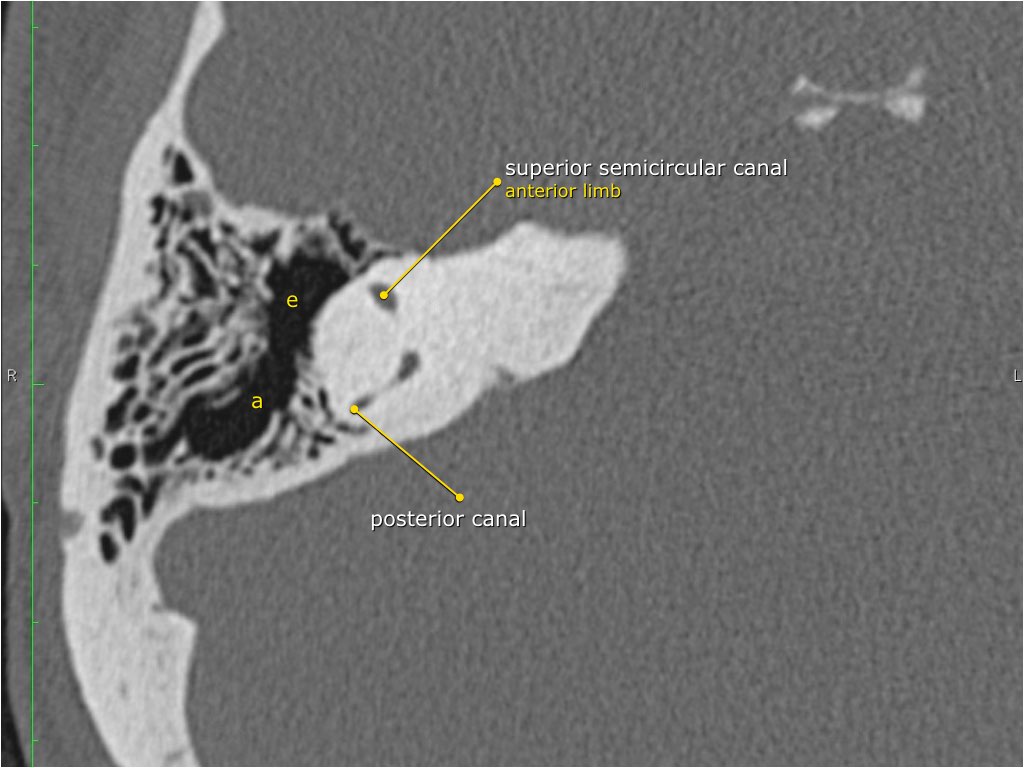

Giải phẫu mặt phẳng coronal của xương đá

Nhấp vào hình ảnh để phóng to.

Cuộn qua các hình ảnh.

Hang bào chũm (Antrum)

Hang bào chũm là một tế bào khí lớn nằm phía trên và phía sau hòm nhĩ, thông với hòm nhĩ qua ngách hang (aditus ad antrum).

Hang bào chũm được bao quanh bởi các tế bào khí chũm nhỏ hơn.